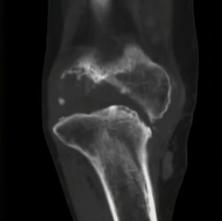

痛风性关节炎骨缺损